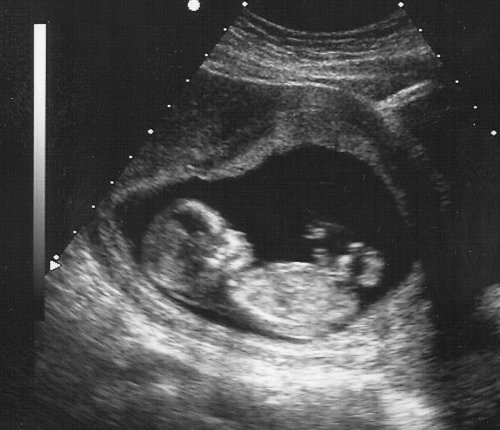

I am now 18 weeks pregnant. Danny and I have talked about keeping the gender a surprise, but I just don't think I can do it until I have one of each! How lame, I know. Tomorrow I have an appt and I might beg my Dr. to tell me the gender. Otherwise I have to wait a whole month! Wah wah.

So I guess you could say I'm definitely showing.

Baby is still cookin' and I have started feeling more and more movements which make Millie's brutally honest comments all worth it.